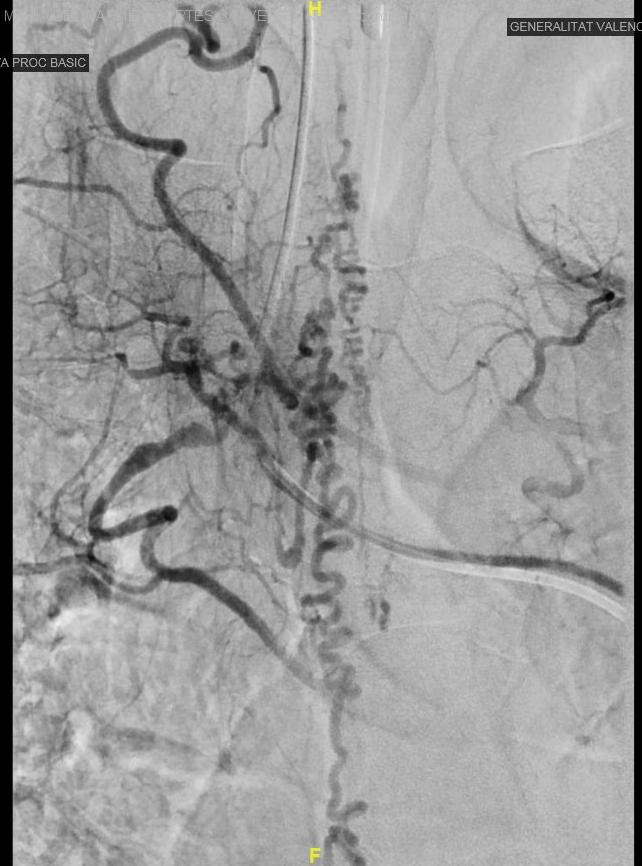

Fístula arteriovenosa dural medular D6. Síndrome sensitivo medular posterior. Infarto medular.

Fístula arteriovenosa dural medular D6. Síndrome sensitivo medular posterior. Infarto medular.

Diagnóstico final: Fístula arteriovenosa dural medular D6. Síndrome sensitivo medular posterior. Infarto medular.

Etiología: Malformación vascular

Varón de 68 años con antecedentes de fibrilación auricular paroxística. Ingresa en Neurología por presentar hipoestesia crural del miembro inferior izquierdo de dos años de evolución, junto con dolor tipo claudicación intermitente neurógena en miembros inferiores. En las últimas...